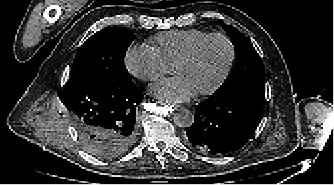

Figura 1: Imagen de tomografía de tórax en proyección axial con ventana de tejidos blandos a nivel de la silueta cardiaca. Se observa en cavidad pleural posterior y derecha, zona heterogénea en densidad con burbujas aisladas que se extiende a través de la pared torácica, condicionando pérdida del plano graso entre la cavidad pleural y la pared del tórax y desplazando lateralmente el músculo dorsal ancho (compárese con el lado contralateral). Diagnóstico: empiema necessitatis.

Paciente masculino de 71 años, diabético, postoperado de cáncer esofágico, el cual cursó con evolución postquirúrgica tórpida, con manejo prolongado en UCI por múltiples complicaciones sistémicas, entre ellas, cuadro neumónico pulmonar que evolucionó a empiema necessitatis. El derrame paraneumónico es una complicación con prevalencia de 40%. Puede complicarse hasta la generación de empiema. Cuando éste se extiende a través de la pleura parietal hacia tejido circundante, formando un trayecto fistuloso y una masa en el tejido extra pleural se denomina “empiema necessitatis”1 (EN). La incidencia actual de EN es rara. Fue descrito por Guillan de Baillon en 1640. La mayoría de los casos reportados son secundarios a infección2 por Mycobacterium tuberculosis, Actinomyces israelii, S. pneumoniae, E. coli, Pseudomonas, Aspergillus, anaerobios y menos frecuente por Staphylococcus aureus. Los factores de riesgo3 son: pacientes inmunocomprometidos con diabetes mellitus tipo 2, alcoholismo crónico, enfermedad pulmonar obstructiva crónica (EPOC) y caquexia. Los estudios de imagen y el cultivo son las herramientas de elección para el diagnóstico; la tomografía es primordial en el diagnóstico. El tratamiento incluye: inicio temprano de antibiótico de amplio espectro, por tres o cuatro semanas y drenaje percutáneo o quirúrgico.4 Debido a la rareza actual del EN no hay reportes de defunciones en la literatura médica mundial, lo que indica una adecuada respuesta al tratamiento.